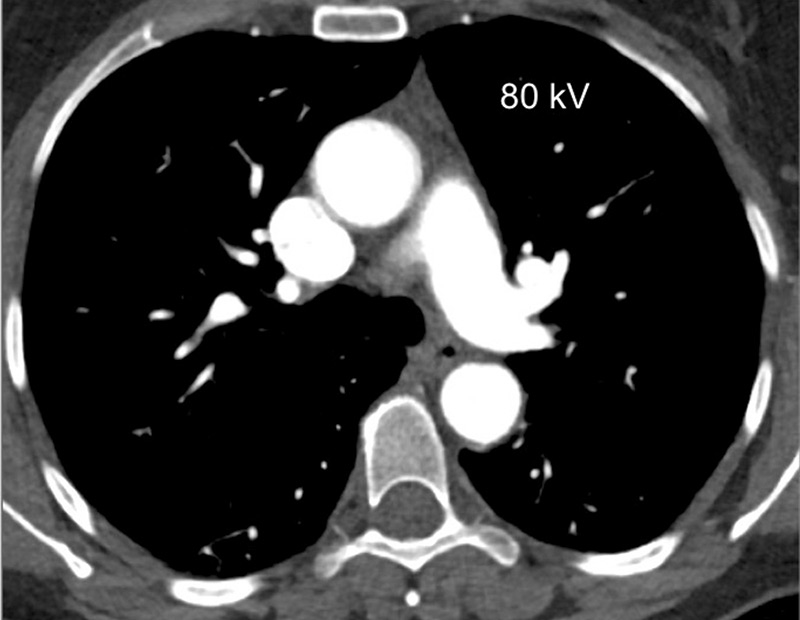

Because of the attenuation properties of iodine at two different photon energies (80 and 140 kV), a dual-energy technique can generate pulmonary blood volume maps and quantify the iodine concentration in the parenchyma. It has been demonstrated that the local distribution of iodine contrast medium correlates well with pulmonary perfusion [18]. The generated pulmonary blood volume maps are combined with mediastinal images to permit simultaneous analysis of the grey-scale vasculature and colour-scale parenchymal perfusion, with parenchymal images (fig. 1). Furthermore, the iodine concentration in the lung allows an objective and quantitative analysis.

Figure 1

Technical principles. The dual-energy system with two X-ray tubes permits simultaneous 80 (A) and 140 kV (B) image acquisition in order to generate an iodine map (C) fused with mediastinal reconstructions (D).